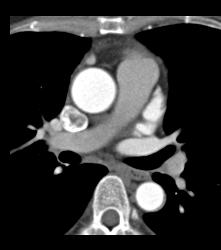

Normal Left Anterior Descending Coronary Artery (LAD)